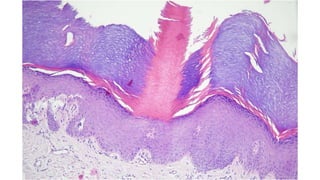

Histopathology of

Porokeratosis

Hereditary disorder of

keratinization characterized by

expanding atrophic anular patch(es)

surrounded by prominent keratotic

ridge called the cornoid lamella